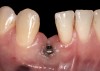

Fig 32. A dissatisfied patient presented with significant midfacial recession of implant restoration of tooth No. 26. Pink ceramic material was used unsuccessfully to prosthodontically compensate for the lost midfacial tissue.

Figure 32

Fig 33. Excessive facial angulation of the implant placement shown with an abutment driver in the access screw hole.

Figure 33

Fig 34. A surgical cover screw was placed in an attempt to decoronate the implant and gain soft-tissue coverage in situ.

Figure 34

The following case report provides an example of this case scenario: A 24-year-old white male presented with congenitally missing tooth No. 26 restored with a single-tooth cement-retained implant restoration. The implant was placed excessively to the facial aspect of the edentulous site and too shallow, and the periodontal phenotype was thin scalloped (Figure 32). In an effort to mimic the lost midfacial soft tissues, pink ceramics were used as a cosmetic facade. Even though the restoration was not in the esthetic zone, the patient was highly displeased with the esthetic outcome and sought remediation.